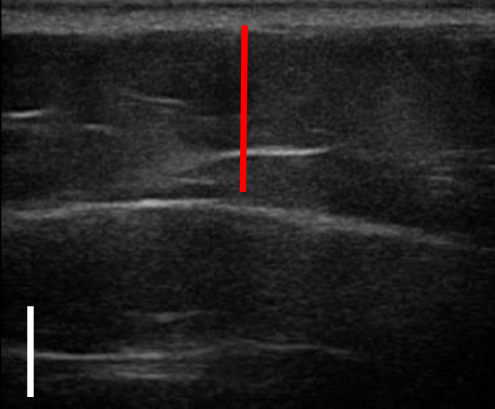

트루스컬프 아이디 시술 전, 12주 후 초음파를 비교한 사진입니다.

위 사례의 경우 지방량이 워낙 많다 보니 시술 후 겉으로 드러난 변화는 적었으나 실제로 감소한 지방량은 상당히 많았습니다.

시술 전과 비교했을 때 약 31% 정도 지방이 감소했습니다.

복부, 옆구리살이 너무 많은 경우 실제 눈에 보이는 것보다 내부에 쌓여있는 지방이 두터운 경우가 많아 시술을 해도 큰 변화를 보이지 않는 경우가 많은데요. 실제로 시술 후 큰 변화가 없어 실망하는 분들도 많지만 위와 같이 초음파 검사를 통해 속을 들여다보면 상당 부분 지방이 감소한 것을 확인할 수 있습니다.